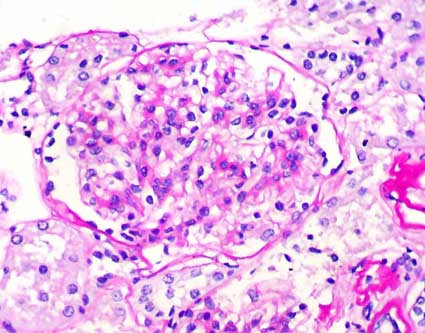

Figura 3.

En algunos glomérulos hay además hipertrofia de podocitos

(Tricrómico de Masson, X400).